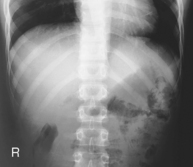

Fig. 7-13 45° RAO above diaphragm—bilateral, right anterior injury (to shift spine away from injury).

One suggested two-image routine is an AP or PA with the area of injury closest to the image receptor (IR) (above or below diaphragm) and an oblique projection of the axillary ribs on the side of injury. Therefore the oblique for this routine on an injury to the left anterior ribs would be an RAO shifting the spine away from the area of injury and to increase visibility of the left axillary ribs. The oblique for an injury to the right posterior ribs would be an RPO wherein the spine again is rotated away from the area of injury.

• Oblique 45°, rotate spine away from area of interest